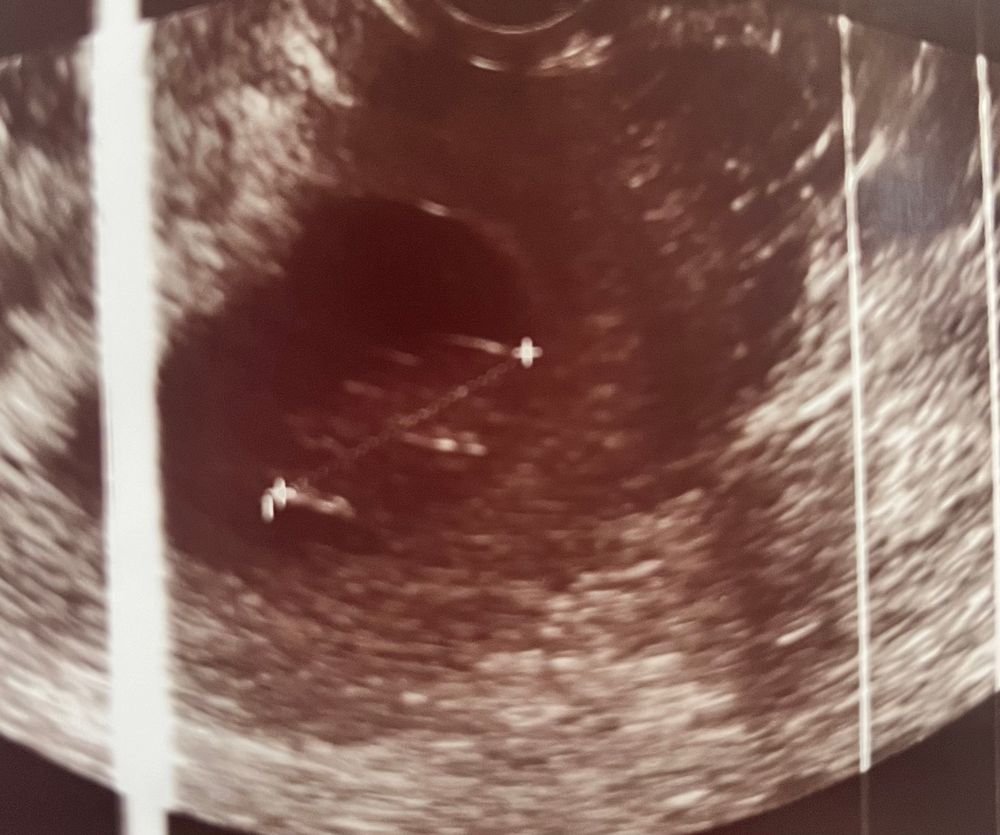

Наши 9-10 нед ❤️

Сегодня была на узи, сказали что все хорошо, показали как ляль болтыхает ножками. Сердцебиение в норме, тонуса нет. Но мне до сих пор не верится…Будто не со мной все происходит.